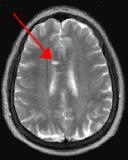

Fig. 1

By turning CSF dark, bright periventricular lesions such as MS plaques become much more conspicuous. Fig. 1 shows a typical T2-weighted axial image of the brain in which CSF in the ventricles appears bright. A lesion on the right is present (red arrow) that is also bright similar to CSF. Fig. 2 is a corresponding FLAIR image showing an obvious bright MS plaque (white arrow) against a background of dark CSF and gray parenchyma with additional more subtle lesions.